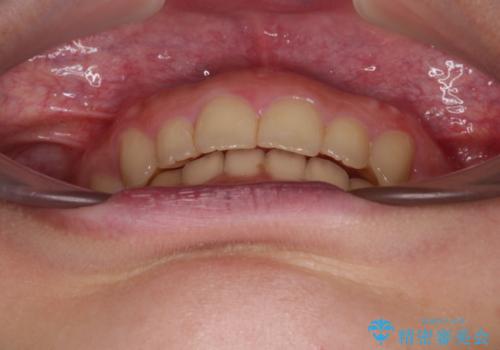

- 深い咬み合わせと上顎前歯の突出感を気にして来院された患者様です。

正面や横からの写真ではきれいに治っており、患者様は大変満足のいく仕上がりとなりましたが、深い咬み合わせの改善は不十分で、奥歯の咬み合わせも改善させることができませんでした。